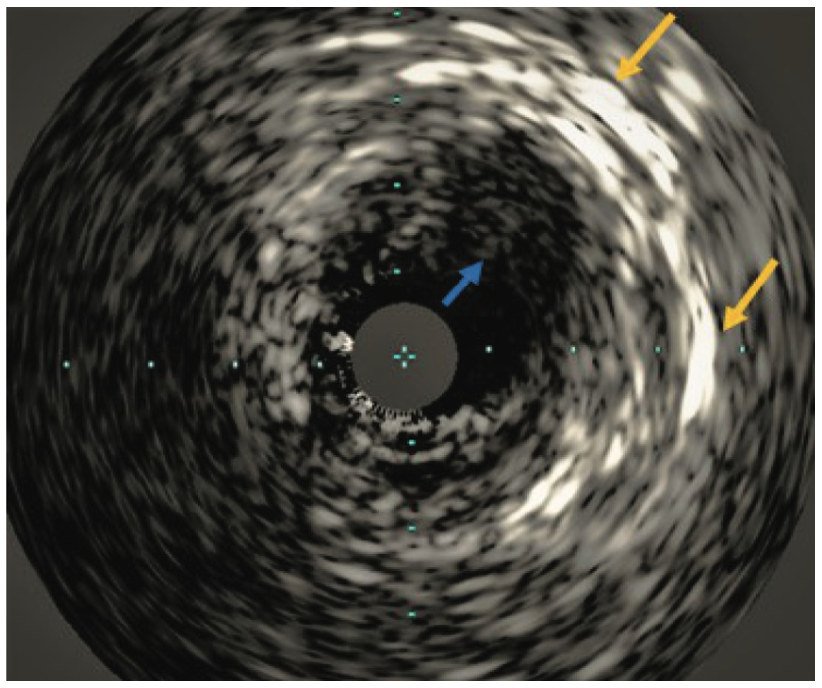

There was also mild to moderate non-obstructive disease of the SVG to the right PDA. The ostial LIMA lesion was validated with the administration of intracoronary nitroglycerin and later with intravascular ultrasound (IVUS) (Figure 1B), as well as by the observation of severe balloon compression during the interventional procedure, as described below.

The native proximal left circumflex artery (TIMI-2 flow pre, type C lesion) had diffuse calcification with a 95% stenosis that was treated successfully with a Diamondback 360˚ coronary orbital atherectomy system (CSI), balloon angioplasty, and Shockwave intravascular lithotripsy with a 3.5 mm x 12 mm C2 balloon using 30 pulses, followed by placement of a Resolute Onyx 3.5 x 26 mm DES (Medtronic) extending back into the left main, and post dilated to >4 mm at high pressure, resulting in 0% residual stenosis with TIMI-3 flow. The OM2 had a 100% functionally occluded competitive vein graft with tortuous flow that was treated successfully with orbital atherectomy, balloon angioplasty, and placement of a Resolute Onyx 2.75 x 26 mm DES extending into the proximal circumflex. The stent was post dilated to high pressure with 0% residual stenosis and TIMI-3 flow post intervention (Figure 4). Intravascular ultrasound (IVUS) was employed for optimal equipment and stent sizing. IVUS also reaffirmed the true significant lesion in the ostia LIMA (Figure 1B, Figure 3B). The patient tolerated the procedure well and was transferred back to general cardiology care, with the addition of aspirin and ticagrelor to her previous medications.

As previously described, arterialization of a venous graft6 with calcium deposition in the vessel wall rather than a plaque may be a case where IVL is preferable over atherectomy. Our case represented an arterial conduit with severe calcification in the vessel wall mixed with soft plaque within the vessel (Figure 1B), in a location where rotational and orbital atherectomy would be ill-advised and potentially compromise the safety of the patient. Intravascular lithotripsy provided effective and safe yielding of the lesion in a LIMA segment with ultimate, optimal DES deployment and expansion.